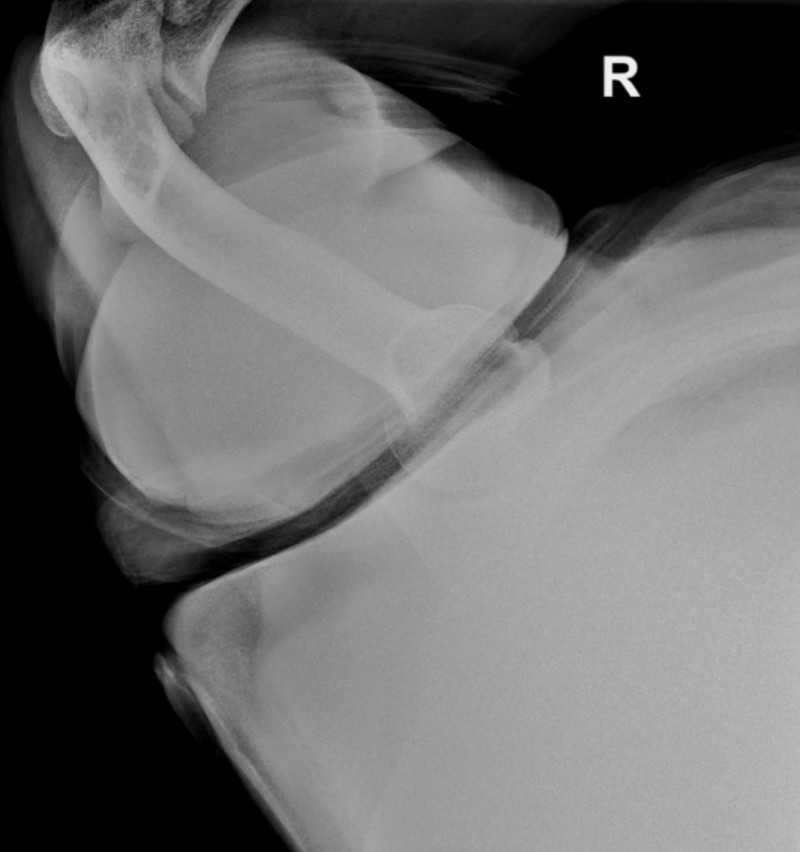

X Ray Posterior Shoulder Dislocation . Posterior dislocation may be missed initially on frontal radiographs in 50% of cases, as the humeral head appears to be almost normally aligned with the glenoid 1,2. Electrocution is a classic but uncommon cause of posterior. Anteroposterior radiograph shows luxatio erecta, or inferior dislocation of the shoulder. The arm is abducted, elevated, and fixed. The axillary lateral view is the most accurate radiographic image to diagnose a posterior shoulder dislocation. Posterior shoulder instability and dislocations are less common than anterior shoulder instability and dislocations, but are much more commonly missed. In adults, convulsive disorders are the most common cause. The humeral head is subcoracoid in. This view eliminates most overlying bony and soft tissue.

In adults, convulsive disorders are the most common cause. The arm is abducted, elevated, and fixed. This view eliminates most overlying bony and soft tissue. The axillary lateral view is the most accurate radiographic image to diagnose a posterior shoulder dislocation. The humeral head is subcoracoid in. Electrocution is a classic but uncommon cause of posterior. Posterior dislocation may be missed initially on frontal radiographs in 50% of cases, as the humeral head appears to be almost normally aligned with the glenoid 1,2. Anteroposterior radiograph shows luxatio erecta, or inferior dislocation of the shoulder. Posterior shoulder instability and dislocations are less common than anterior shoulder instability and dislocations, but are much more commonly missed.

X Ray Posterior Shoulder Dislocation Anteroposterior radiograph shows luxatio erecta, or inferior dislocation of the shoulder. Electrocution is a classic but uncommon cause of posterior. Anteroposterior radiograph shows luxatio erecta, or inferior dislocation of the shoulder. Posterior dislocation may be missed initially on frontal radiographs in 50% of cases, as the humeral head appears to be almost normally aligned with the glenoid 1,2. The arm is abducted, elevated, and fixed. The humeral head is subcoracoid in. In adults, convulsive disorders are the most common cause. The axillary lateral view is the most accurate radiographic image to diagnose a posterior shoulder dislocation. This view eliminates most overlying bony and soft tissue. Posterior shoulder instability and dislocations are less common than anterior shoulder instability and dislocations, but are much more commonly missed.